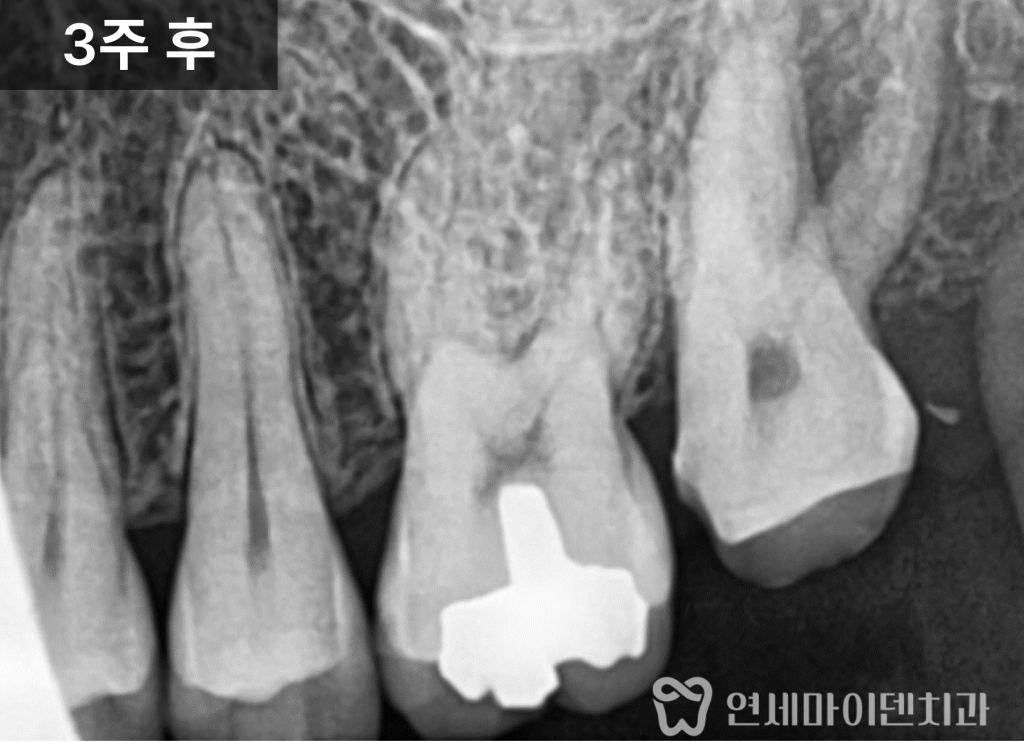

추가 엑스레이에서

치아 주변 뼈가 녹아 있는 소견이 나타났습니다.

초기 내원 당시에는 없던 변화였지만

불과 2~3주 사이에 급격하게 진행된 상태였습니다.

신경치료 후 크라운, 뼈는 다시 회복될까

치아를 살릴 수 있는 가능성이 있다고 판단해

신경치료를 먼저 진행하고

경과를 지켜보기로 했습니다.

이후 크라운으로 수복하여

치아를 보호하면서

뼈의 회복 여부를 관찰했습니다.

시간이 지나면서

초기에 녹아 있던 뼈는

점차 다시 차오르는 양상이 확인되었습니다.